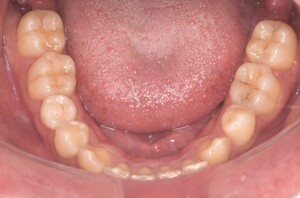

症例4

before

症例

after

抜歯前

抜歯後

基本情報

年齢・性別 26歳・男性

主訴 主訴:左下親知らず痛い

治療部位:左下8番

治療内容 ・左下8番埋伏抜歯

〈歯周病治療〉

①検査、資料取り(歯周ポケット検査、レントゲン14枚法、口腔内写真)、染めだし、歯磨き指導

②歯肉縁上の歯石除去、歯磨き指導、確認

③歯肉縁下の歯石除去(SRP)

④再評価

⑤メインテナンス

治療方針 左下の親知らずが痛いとのことでご来院された患者さまです。

親知らず周囲は汚れが落としきれておらず、歯ぐきが炎症を起こしている状態でした。

当日抜歯を希望されていたので、麻酔を効かせてから三次元的なレントゲン写真(CT)撮影し、抜歯を行いました。

その後、全顎的に歯石付着、歯ぐきの炎症が見られたので歯周病治療をその他の治療と並行して行っていきました。

担当者所見 初診時は歯ブラシの交換時期を把握していなかった患者さまが歯ブラシを新しくしてから約1ヶ月後自分から歯ブラシを変えたことを教えてくださいました。

歯周病治療を進めていくうちに、患者さまの口腔内への意識が高まっていて治療が良い方向に進んでいきました。

歯周基本治療とセルフケアで歯ぐきの炎症や出血は初診時より大分改善されましたが、出血率を0%まで減らしていけるように今後は定期的な検診で歯ブラシの当て方や経過を患者さまと一緒に確認していこうと思います。